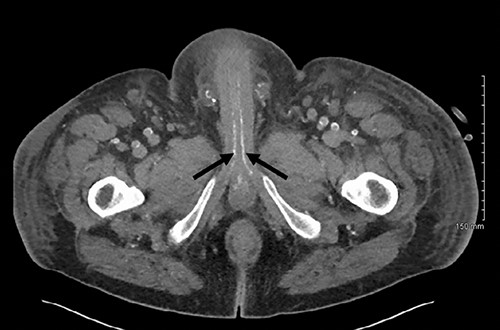

Axial slice of a non-contrast CT AP with red arrows showing calcified external iliac arteries and black arrows showing calcified internal iliac arteries.

Post-operatively the patient was experiencing ongoing severe penile, examination of the glans was not possible due to oedema and pain. Our patient underwent dialysis to offload excess fluid. A CT angiogram revealed extensive peripheral vascular arterial calcification, including calcification of the internal pudendal and cavernosal arteries (Figs 2 and 3). The inguinal lymphadenopathy was shown to be reactive.

The gold standard for the diagnosis remains skin biopsy. Biopsy of the foreskin at the time of dorsal slit did not elucidate any calciphylaxis, however did out rule malignancy. Glansectomy and circumcision confirmed calciphylaxis with vessel calcification and necrosis. However, often times diagnosis is made based on presentation, bloods and imaging, due to the risk of biopsy potentiating infection. Radiological investigations can aid diagnosis. CT is the most sensitive, assessing the extent of vascular calcification, as in our case [1] (Figs 2 and 3).